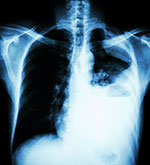

Breathing asbestos can cause tiny asbestos fibers to get stuck in the lungs and irritate lung tissues.

Scientific studies have shown that the following non-cancer diseases can be caused by breathing asbestos: